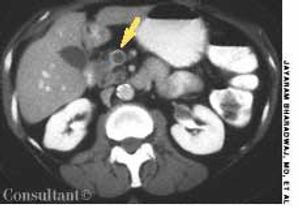

A 65-year-old woman with metastatic adenocarcinoma of the colon was undergoing chemotherapy following a colectomy and a hepatic wedge resection. The physical examination and laboratory data were unremarkable.